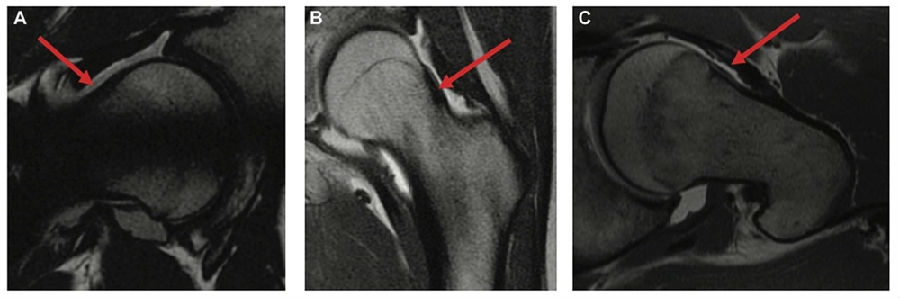

3.3青少年患者软组织型Cam

FAI患者股骨侧Cam的评估以往主要借助髋关节X线片和三维CT进行评估,然而,Youngman TR等[11]近期在AJSM上发表,青少年患者股骨的头颈交界区可能存在由软骨、纤维组织等构成的非骨性的凸轮畸形,而这种类型的非骨性的凸轮在X线片和三维CT等放射学影像上不会显示。因此,对于青少年患者,我们更应该仔细判读患者的MR影像,评估头颈交界区是否有软组织型的凸轮畸形。

图4:青少年患者MR显示头颈交界区软组织型凸轮畸形[11]

11. Youngman TR, Johnson BL, Morris WZ, Montanez B, Serbin PA, Wagner KJ, 3rd, Wilson PL, Alizai H, Ellis HB, Jr.: Soft Tissue Cam Impingement in Adolescents: MRI Reveals Impingement Lesions Underappreciated on Radiographs. Am J Sports Med 2023, 51(14):3749-3755.